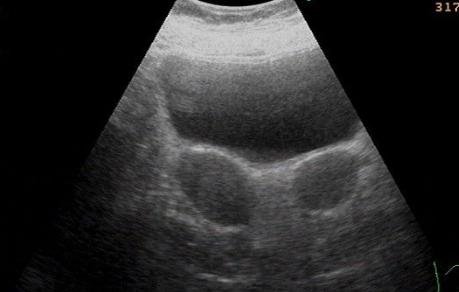

双子宫是指子宫两侧副中肾管在胚胎分裂发育的时候没有融合完全,导致其各自发育形成两个子宫和两个宫颈,双子宫的病例很少,一般是在人工流产,产检的时候偶然发现,双子宫畸形的症状一般有哪些症状呢?

而患者可无任何症状,一般在人工流产、产前检查,甚至分娩时偶然发现。经B超检查,可使双子宫“真相大白”。该病一般不影响结婚和生育,如双子宫合并阴道纵隔,婚后可出现*交性**障碍或*交性**痛,应及时做手术切除纵隔。